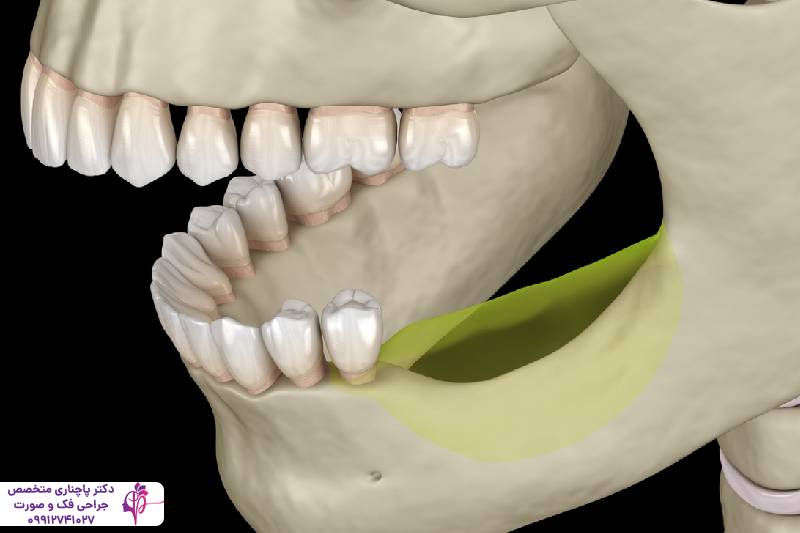

ایمپلنت دندان یکی از موثرترین روشها برای درمان تحلیل استخوان فک و جلوگیری از پیشروی آن است. پایههای تیتانیومی ایمپلنت مثل ریشه دندان طبیعی عمل میکند و با تحریک بافت استخوان جلوی تحلیل رفتن آن را میگیرد. گرچه کاشت ایمپلنت به یک بستر قوی و مناسب نیاز دارد و در صورتی که استخوان فک تراکم خود را از دست داده باشد باید با درمانهای جانبی مثل پیوند استخوان بستر مناسب برای کاشت ایمپلنت را آماده کرد.

پیوند استخوان

پیوند استخوان یکی از کلیدیترین روشها برای درمان تحلیل شدید استخوان فک است. در این فرآیند بافت استخوانی جدید را به ناحیه آسیبدیده اضافه میکنند. این بافت استخوانی جدید هم میتواند از بدن خود بیمار باشد که معمولا با پیوند استخوان فک لگن انجام میشود، یا باید از منابع صنوعی یا حیوانی باشد. این بافت جدید به تدریج با استخوان طبیعی فرد ادغام میشود و حجم و تراکم استخوان به حالت طبیعی برمیگردد. معمولا بعد از پیوند استخوان فک ایمپلنت انجام میشود ولی دوره نقاهت پیوند استخوان باید کامل شود و بعد ایمپلنت انجام دهند.